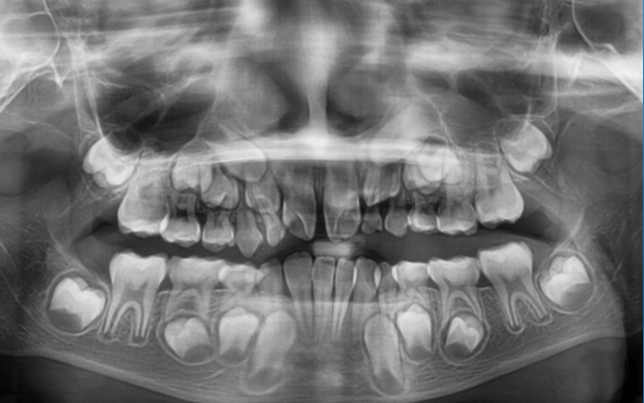

早期矯正治療 埋伏歯症例②

主訴 | 上顎前歯の位置異常に不安を抱え、歯並びと将来的な咬合状態を整える目的で来院された患者様です。 特に左側の前歯(中切歯および側切歯)の萌出が確認できないことがきっかけとなりました。 |

診断結果 | 8歳3か月の男児。 左上1番(中切歯)と左上2番(側切歯)が埋伏し、発育方向にも異常が認められました。加えて、一部先天性欠如も確認されており、歯列全体の成長に影響を及ぼす可能性があると診断されました。 |

治療内容 |

|

治療後の経過 | 動的治療後は3〜4か月ごとの定期検診を行い、上下顎の骨の成長や第二大臼歯の萌出状況を確認しながら、本格的な矯正治療を行う |

治療期間 | 動的治療期間:約5年10か月 |

治療費用 | 460,000円(税別) |